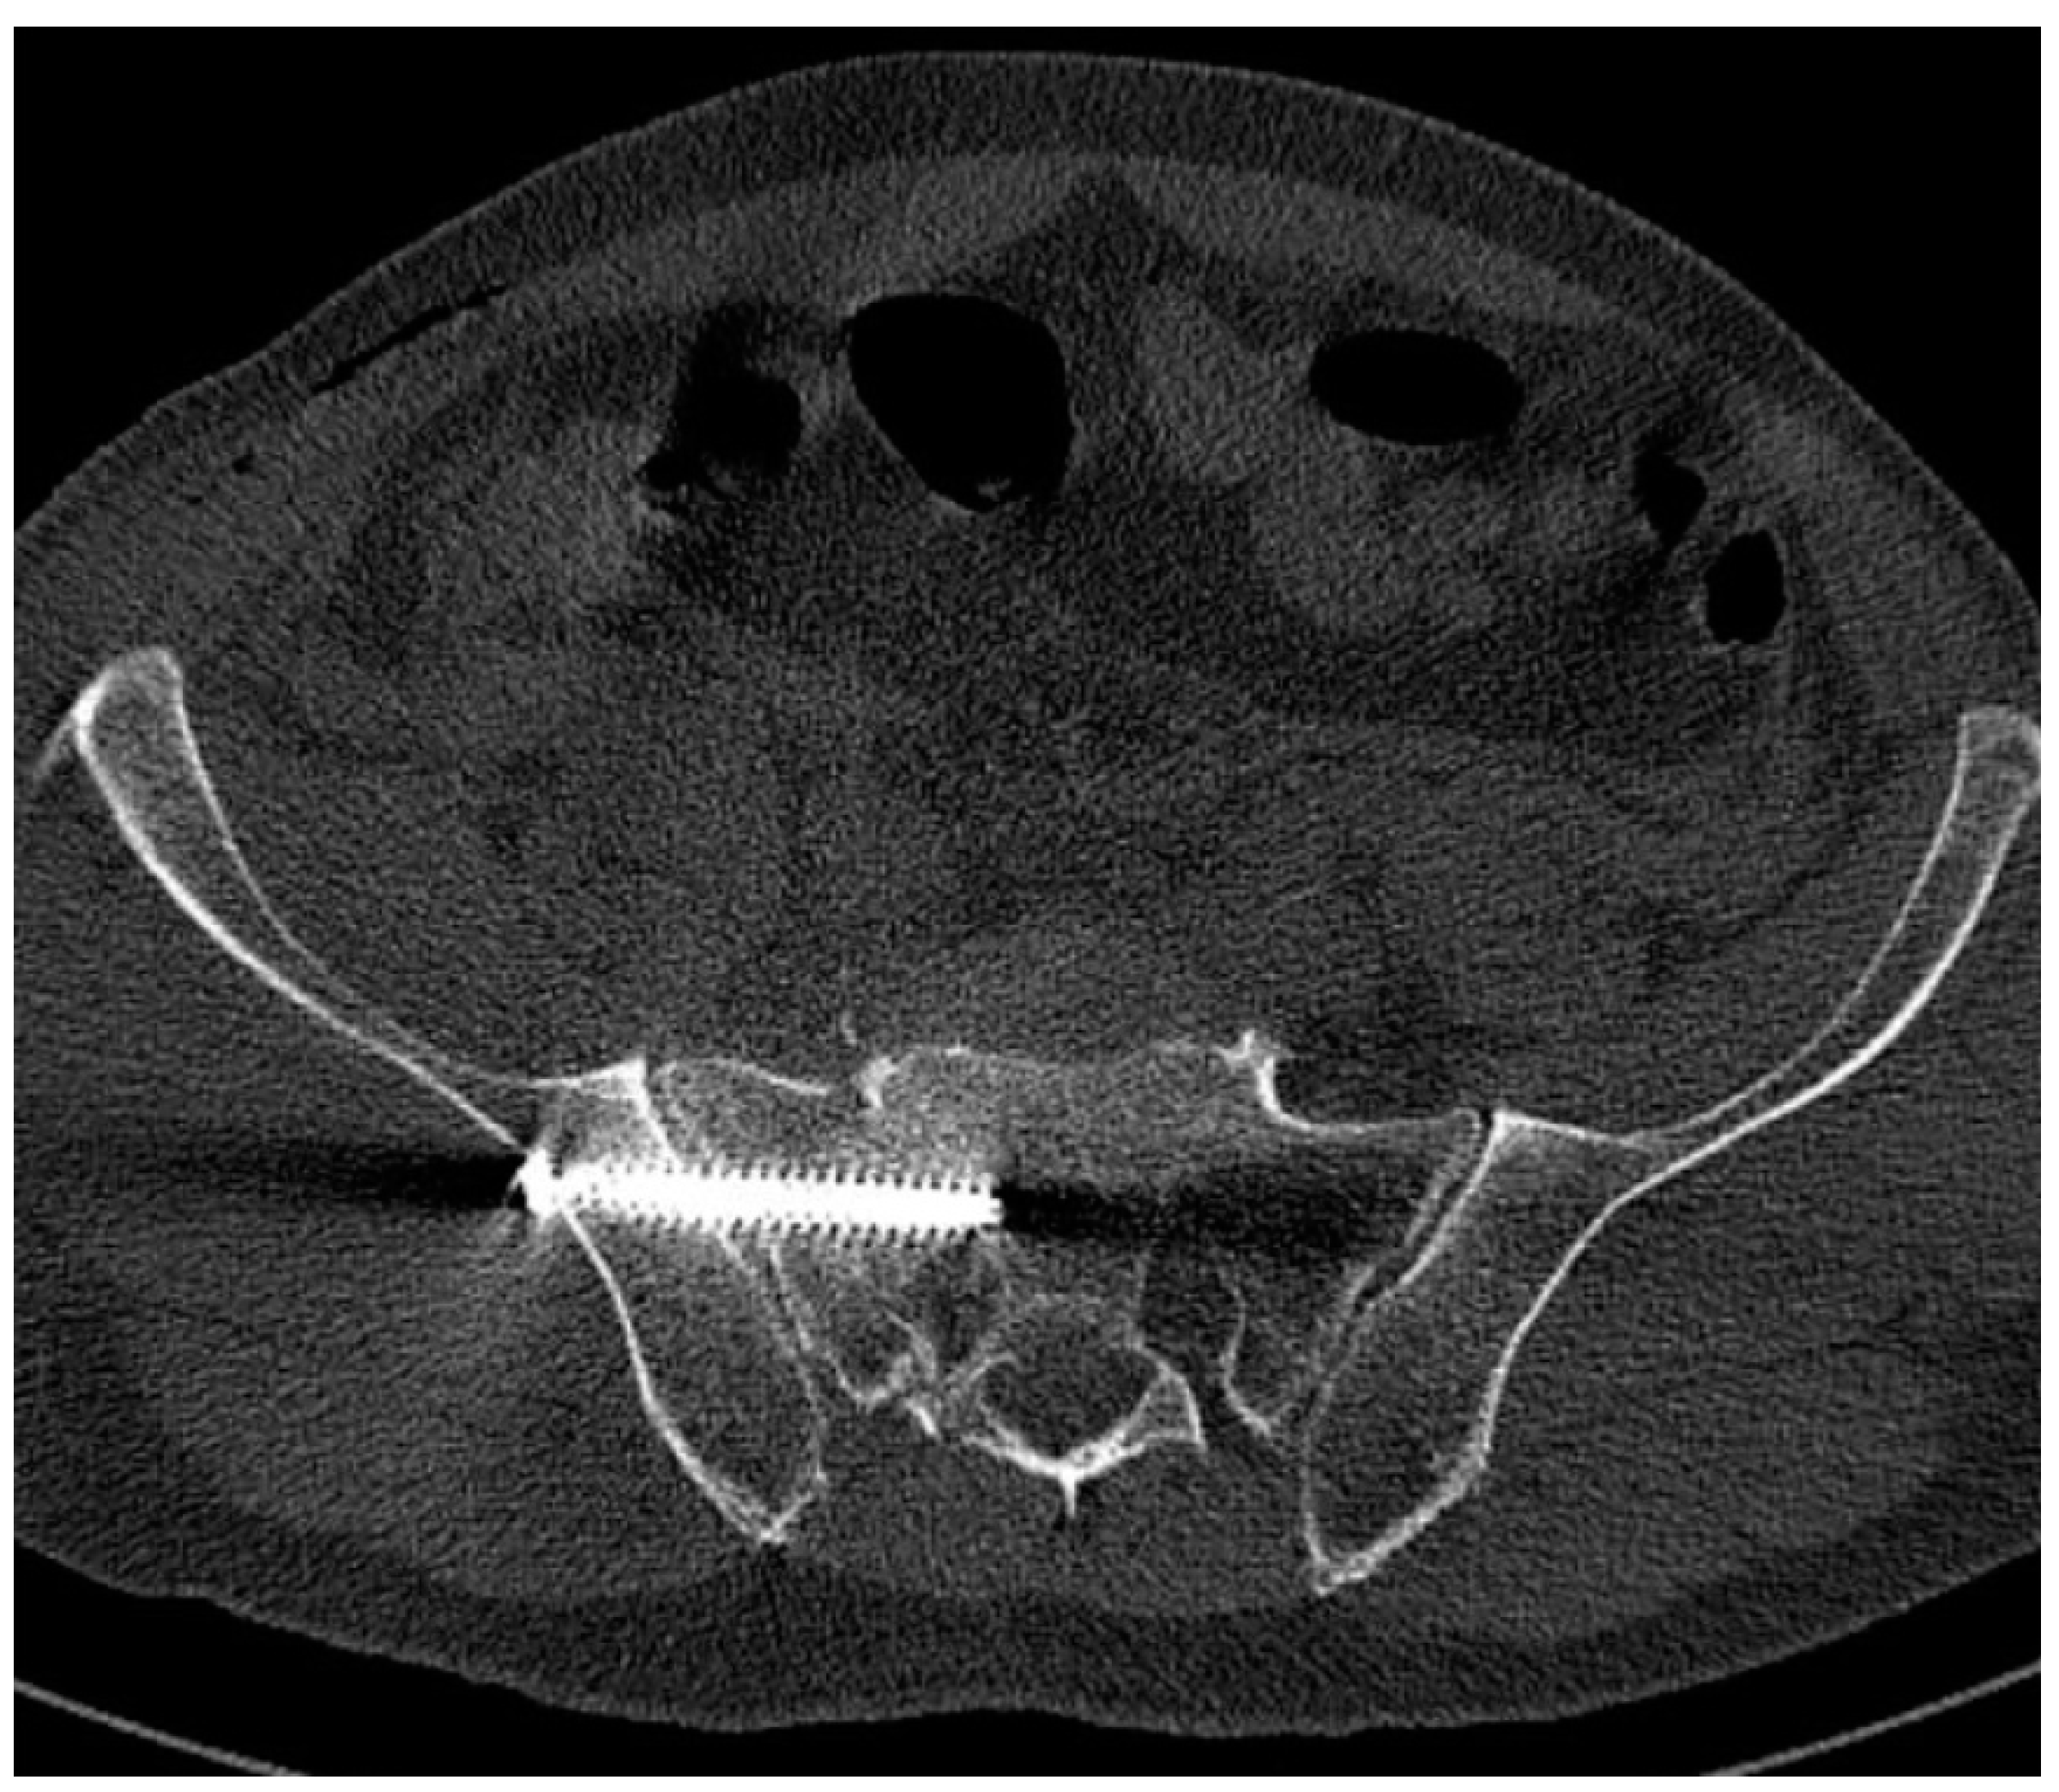

3.2. Number, Localization, and Correct Position of Fixation Screws